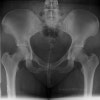

- Radiology : Spine X-ray, MRI 사진은 위양성인 경우가 많으나 고관절 X-ray는 위양성인 경우가 적어 진단에 매우 유익합니다.